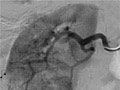

Angiografía de un riñón normal